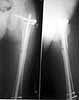

We managed to get neutral phosphate, initiated medical treatment and did an antegrade SIGN nailing of left femur along with couple of screws to neck using miss a nail technique. He complained of pain of the right femur and both forearms. In OT these areas were screened using image intensifier and found that he has looser zones of all these with impending fractures. Yesterday we did a retrograde nailing of right femur usingSIGN nail. Both ulnas were stabilised usingLambrudini wires in a closed fashion. All fractures and looser zones were stabilised by closed surgery using image intensifier. It may be interesting to see the post of picture of both the hips in which one side shows an antegrade femoral SIGN nail and the other side shows a retrograde SIGN nail.